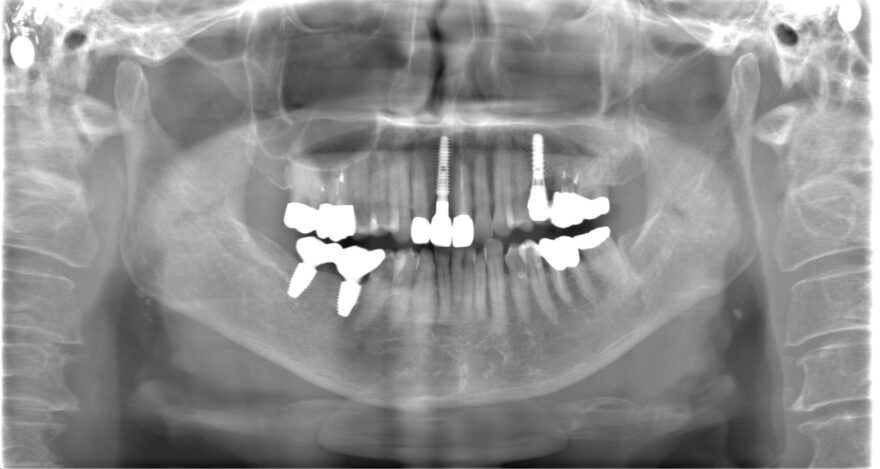

初診時レントゲン写真

このように、前歯の欠損部にブリッジもしくは入れ歯を他院さんで提案されてしまい、当院にご相談に来られる患者様が多数いらっしゃいます。

治療後のレントゲン写真

精密に施術されたインプラントは20年30年とトラブルなくお使い頂けます。